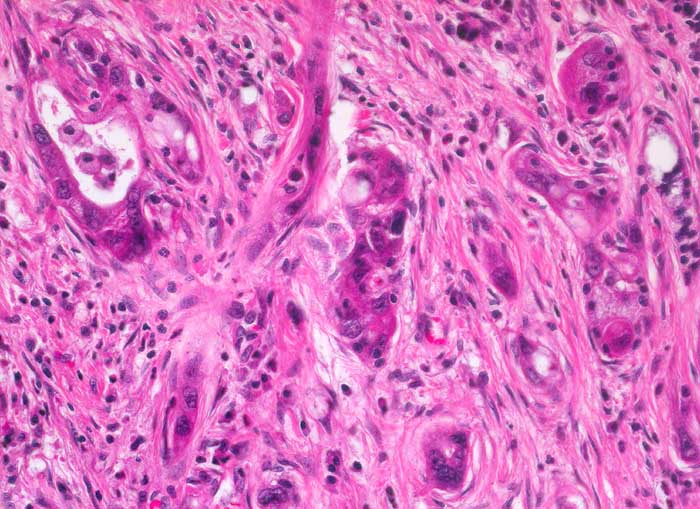

duktales Adenokarzinom des Pankreas

Das Karzinom bildet schlecht geformte oder unvollständige drüsige Strukturen mit ausgeprägten Epithelatypien. Daneben infiltrieren Tumorzellen das Stroma einzeln oder in kleinen Gruppen .

Unregelmässig geformte Drüsen mit unvollständigen Lumina und Einzelzellen oder Gruppen von atypischen Zellen, die das Stroma infiltrieren sind typisch für das Karzinom und sprechen gegen entzündlich bedingte Veränderungen.

Histologie

200